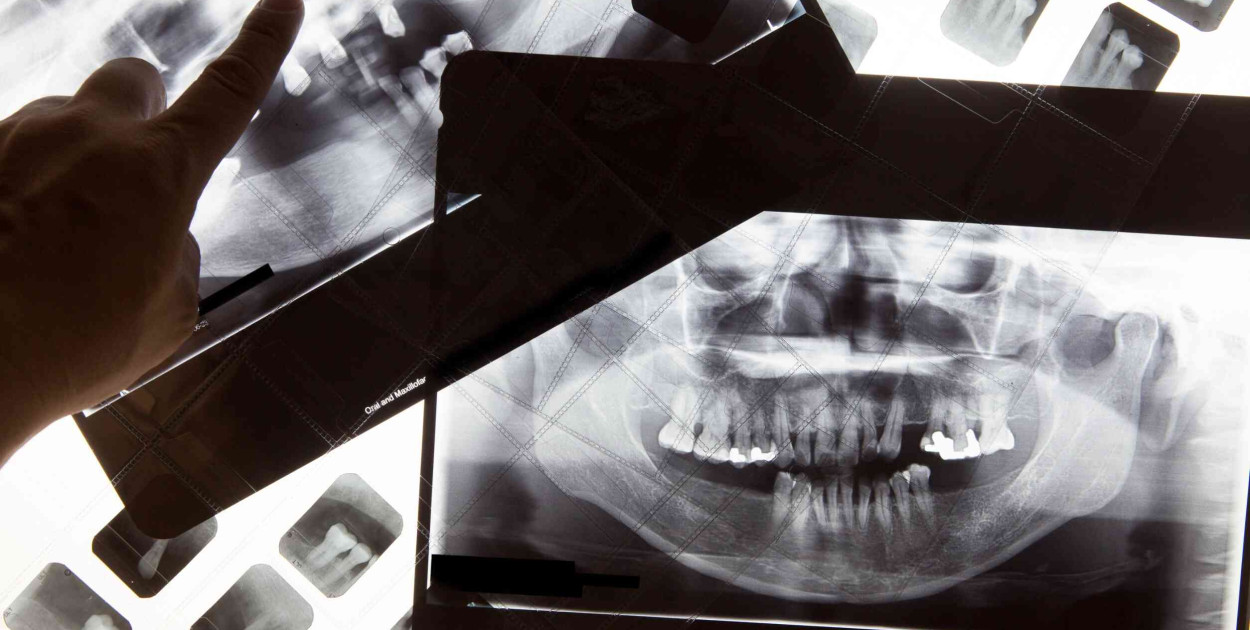

Pantomogram jest nazywany inaczej panoramicznym zdjęciem zębów lub szczęki. Jest to rodzaj zdjęcia rentgenowskiego, które uwidacznia zęby, szczękę i żuchwę oraz otaczające je tkanki miękkie. Do wykonania badania wykorzystuje się promieniowanie RTG oraz rejestrator. Badanie odbywa się w gabinecie stomatologicznym lub ortodontycznym w celu diagnostyki lub oceny postępów leczenia dentystycznego.

Badanie pantomogramem należy do jednych z najbardziej precyzyjnych metod diagnostycznych. Uzyskany w ten sposób obraz pozwala lekarzowi ocenić stan uzębienia pacjenta oraz wykryć większość nieprawidłowości i schorzeń zębów i otaczających ich tkanek. Wśród możliwych do wykrycia zmian chorobowych znajdują się także schorzenia w okolicach okołowierzchołkowych zębów oraz zmiany w zatokach szczękowych.

Na podstawie fotografii lekarz może także sprawdzić stan wypełnienia kanałów korzeniowych w zębach, które są leczone endodontycznie. Metoda pozwala także ocenić nieprawidłowości w budowie zębów lub w stawach skroniowo-żuchwowych. Jest także wykorzystywana podczas wyrzynania się ósemek, które często powodują przesuwanie się pozostałych zębów. Precyzyjny obraz zapewnia dokładną wiedzę na temat rozmieszczenia i stanu struktur, dzięki czemu stomatolog może dobrać odpowiednią technikę leczenia i prowadzenia pacjenta.

Pantomogram ma ogromne znaczenie w diagnostyce stomatologicznej. Istnieją także inne wskazania do wykonania zdjęcia. Wśród nich na pewno znajduje się leczenie ortodontyczne. Na podstawie uzyskanego obrazu lekarz określa sposób rozmieszczenia zębów, stan uzębienia oraz ewentualną wadę zgryzu lub nieprawidłowości w wyrzynaniu się zębów. Dzięki zdobytej w ten sposób wiedzy na temat szczęki pacjenta jest w stanie dopasować odpowiedni aparat ortodontyczny.

Zdjęcie panoramiczne zębów wykonywane jest w trakcie leczenia pacjenta z zaawansowaną próchnicą. Widoczny nalot może być wierzchołkiem problemu, który może sięgać znacznie głębszych kieszonek zębowych. Metoda pozwala także ustalić, które z zębów mogą być jeszcze leczone zachowawczo, a które wymagają większej ingerencji lub powinny zostać usunięte. Zdjęcie RTG wykorzystywane jest także w terapii chorób przyzębia. Panoramiczny obraz szczeki pozwala m.in. ocenić stopień paradontozy i dobrać do niego odpowiednią technikę leczenia. Wskazaniem do wykonania pantomogramu szczęki są także urazy żuchwy, które mogą skutkować przemieszczeniem się lub utratą zębów. Wykonuje się je także przed planowym zabiegiem usuwania.